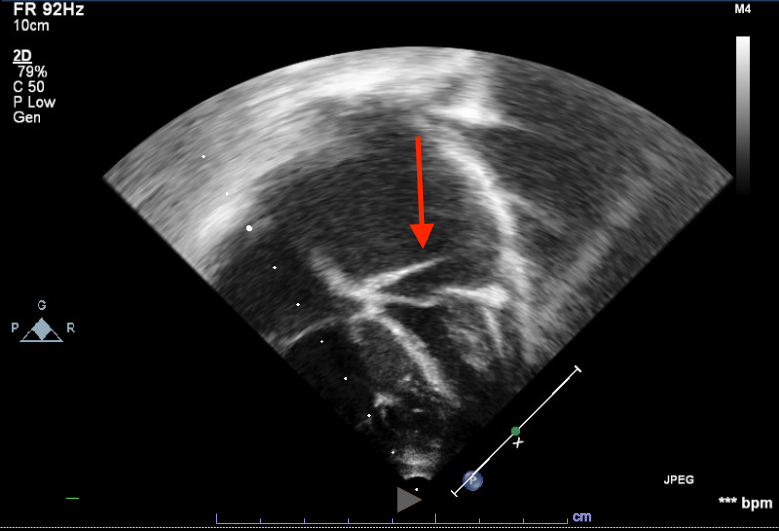

Due to FTT diagnosis, gastroenterology was consulted. Testing for food intolerances and malabsorptive processes was initiated which was unrevealing. He had 1.5kg weight gain over three days and developed facial edema, hepatomegaly and tachypnea, so IV fluids were discontinued. Chest x-ray showed pulmonary venous congestion, ECG revealed possible left atrial enlargement, and BNP was elevated at 2,286 pg/mL. Echocardiogram revealed cor triatriatum sinistrum. Pediatric cardiology was consulted, and the patient was diuresed with furosemide. After reaching euvolemia, he was discharged home and followed closely. He underwent surgical resection of left atrial membrane. Post-operative course was uncomplicated and FTT resolved.

Discussion: Cor triatriatum sinistrum (CTS) is a rare heart defect, and may be associated with other cardiac defects. Embryologically, CTS is attributed to failure of the common pulmonary vein being incorporated into the left atrium. This results in functional division of the atrium into two chambers by a thin fibromuscular membrane which causes a variable, and sometimes progressive, obstruction of flow in the left atrium.

CTS may present at nearly any age, with cases of more severe obstruction presenting during infancy. Typical presenting symptoms include activity intolerance, cyanosis, respiratory distress, murmur, and cardiogenic shock. In this case the pulmonary venous congestion resulted in symptoms of tachypnea and FTT more commonly seen with pulmonary over circulation in left to right shunts such as ventricular septal defects. Diagnosis may be made with transthoracic echocardiography.